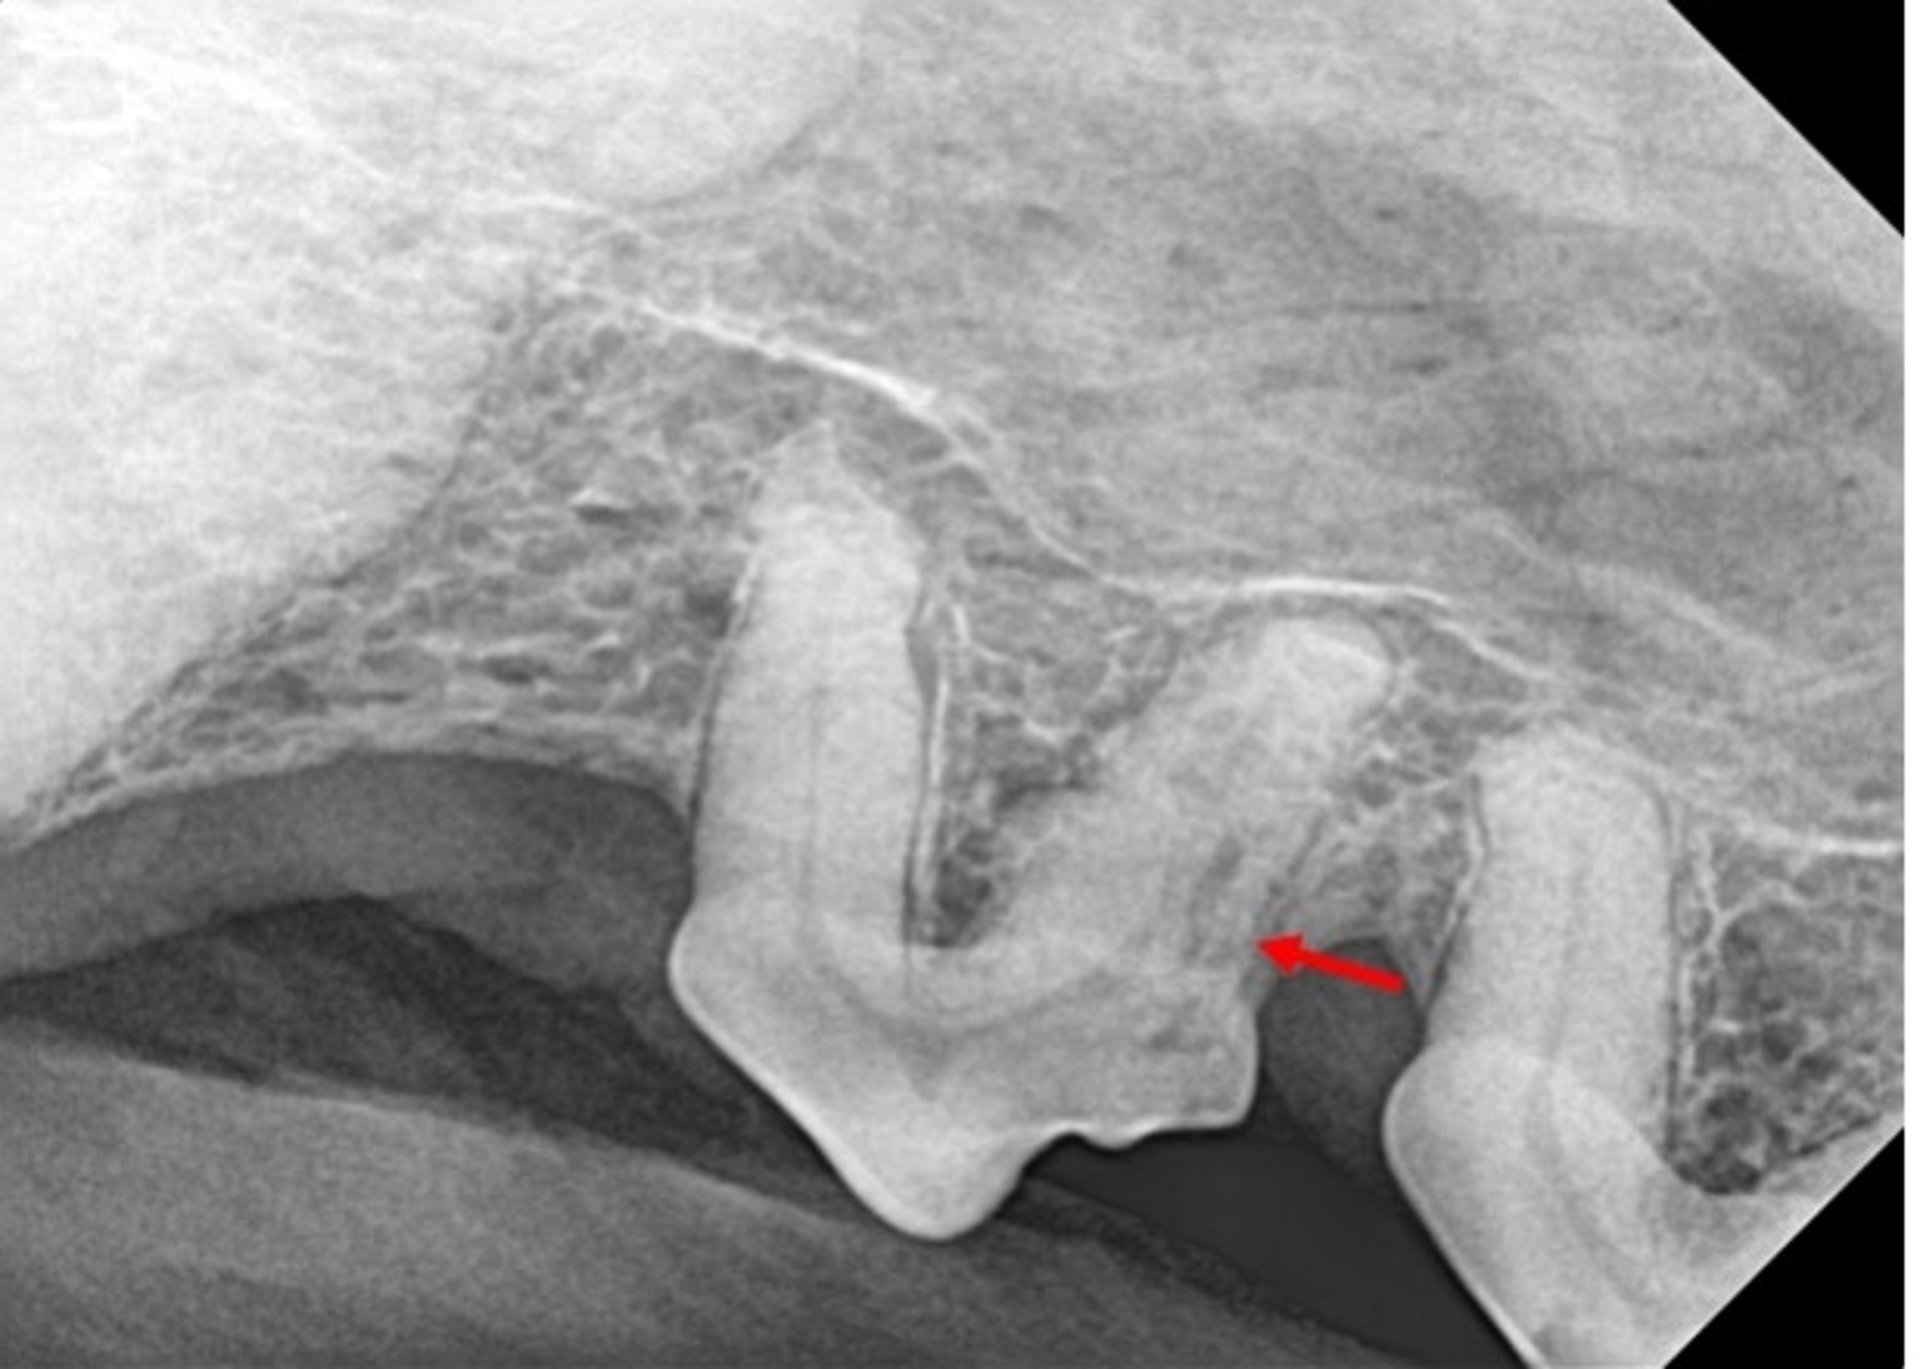

La reabsorción dental interna solo puede observarse radiográficamente dentro del diente. Esta radiografía muestra evidencia de reabsorción dental en la raíz distal del segundo premolar maxilar izquierdo de un perro.

Cortesía de la Dra. Brenda Mulherin.